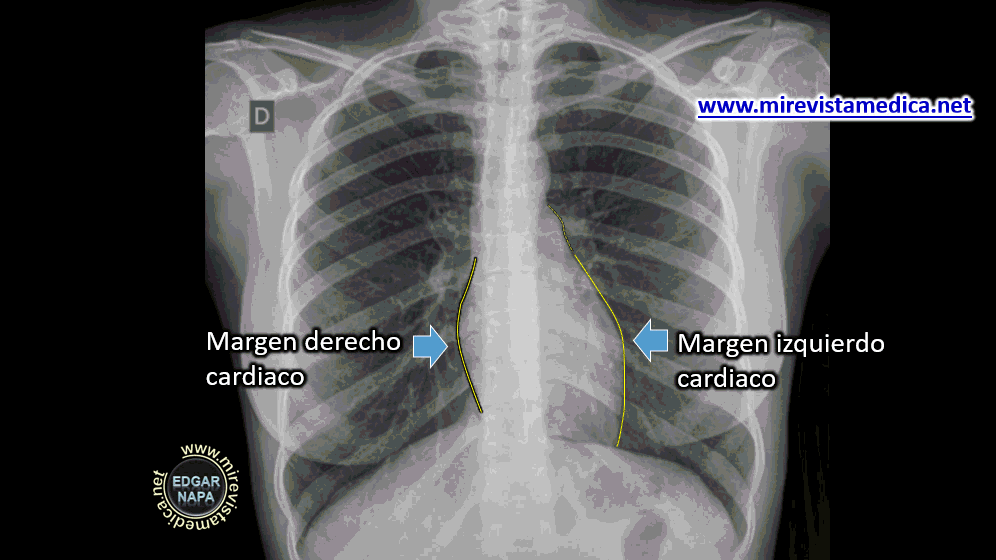

SILUETA ​​CARDIACA EN RADIOGRAFÍA